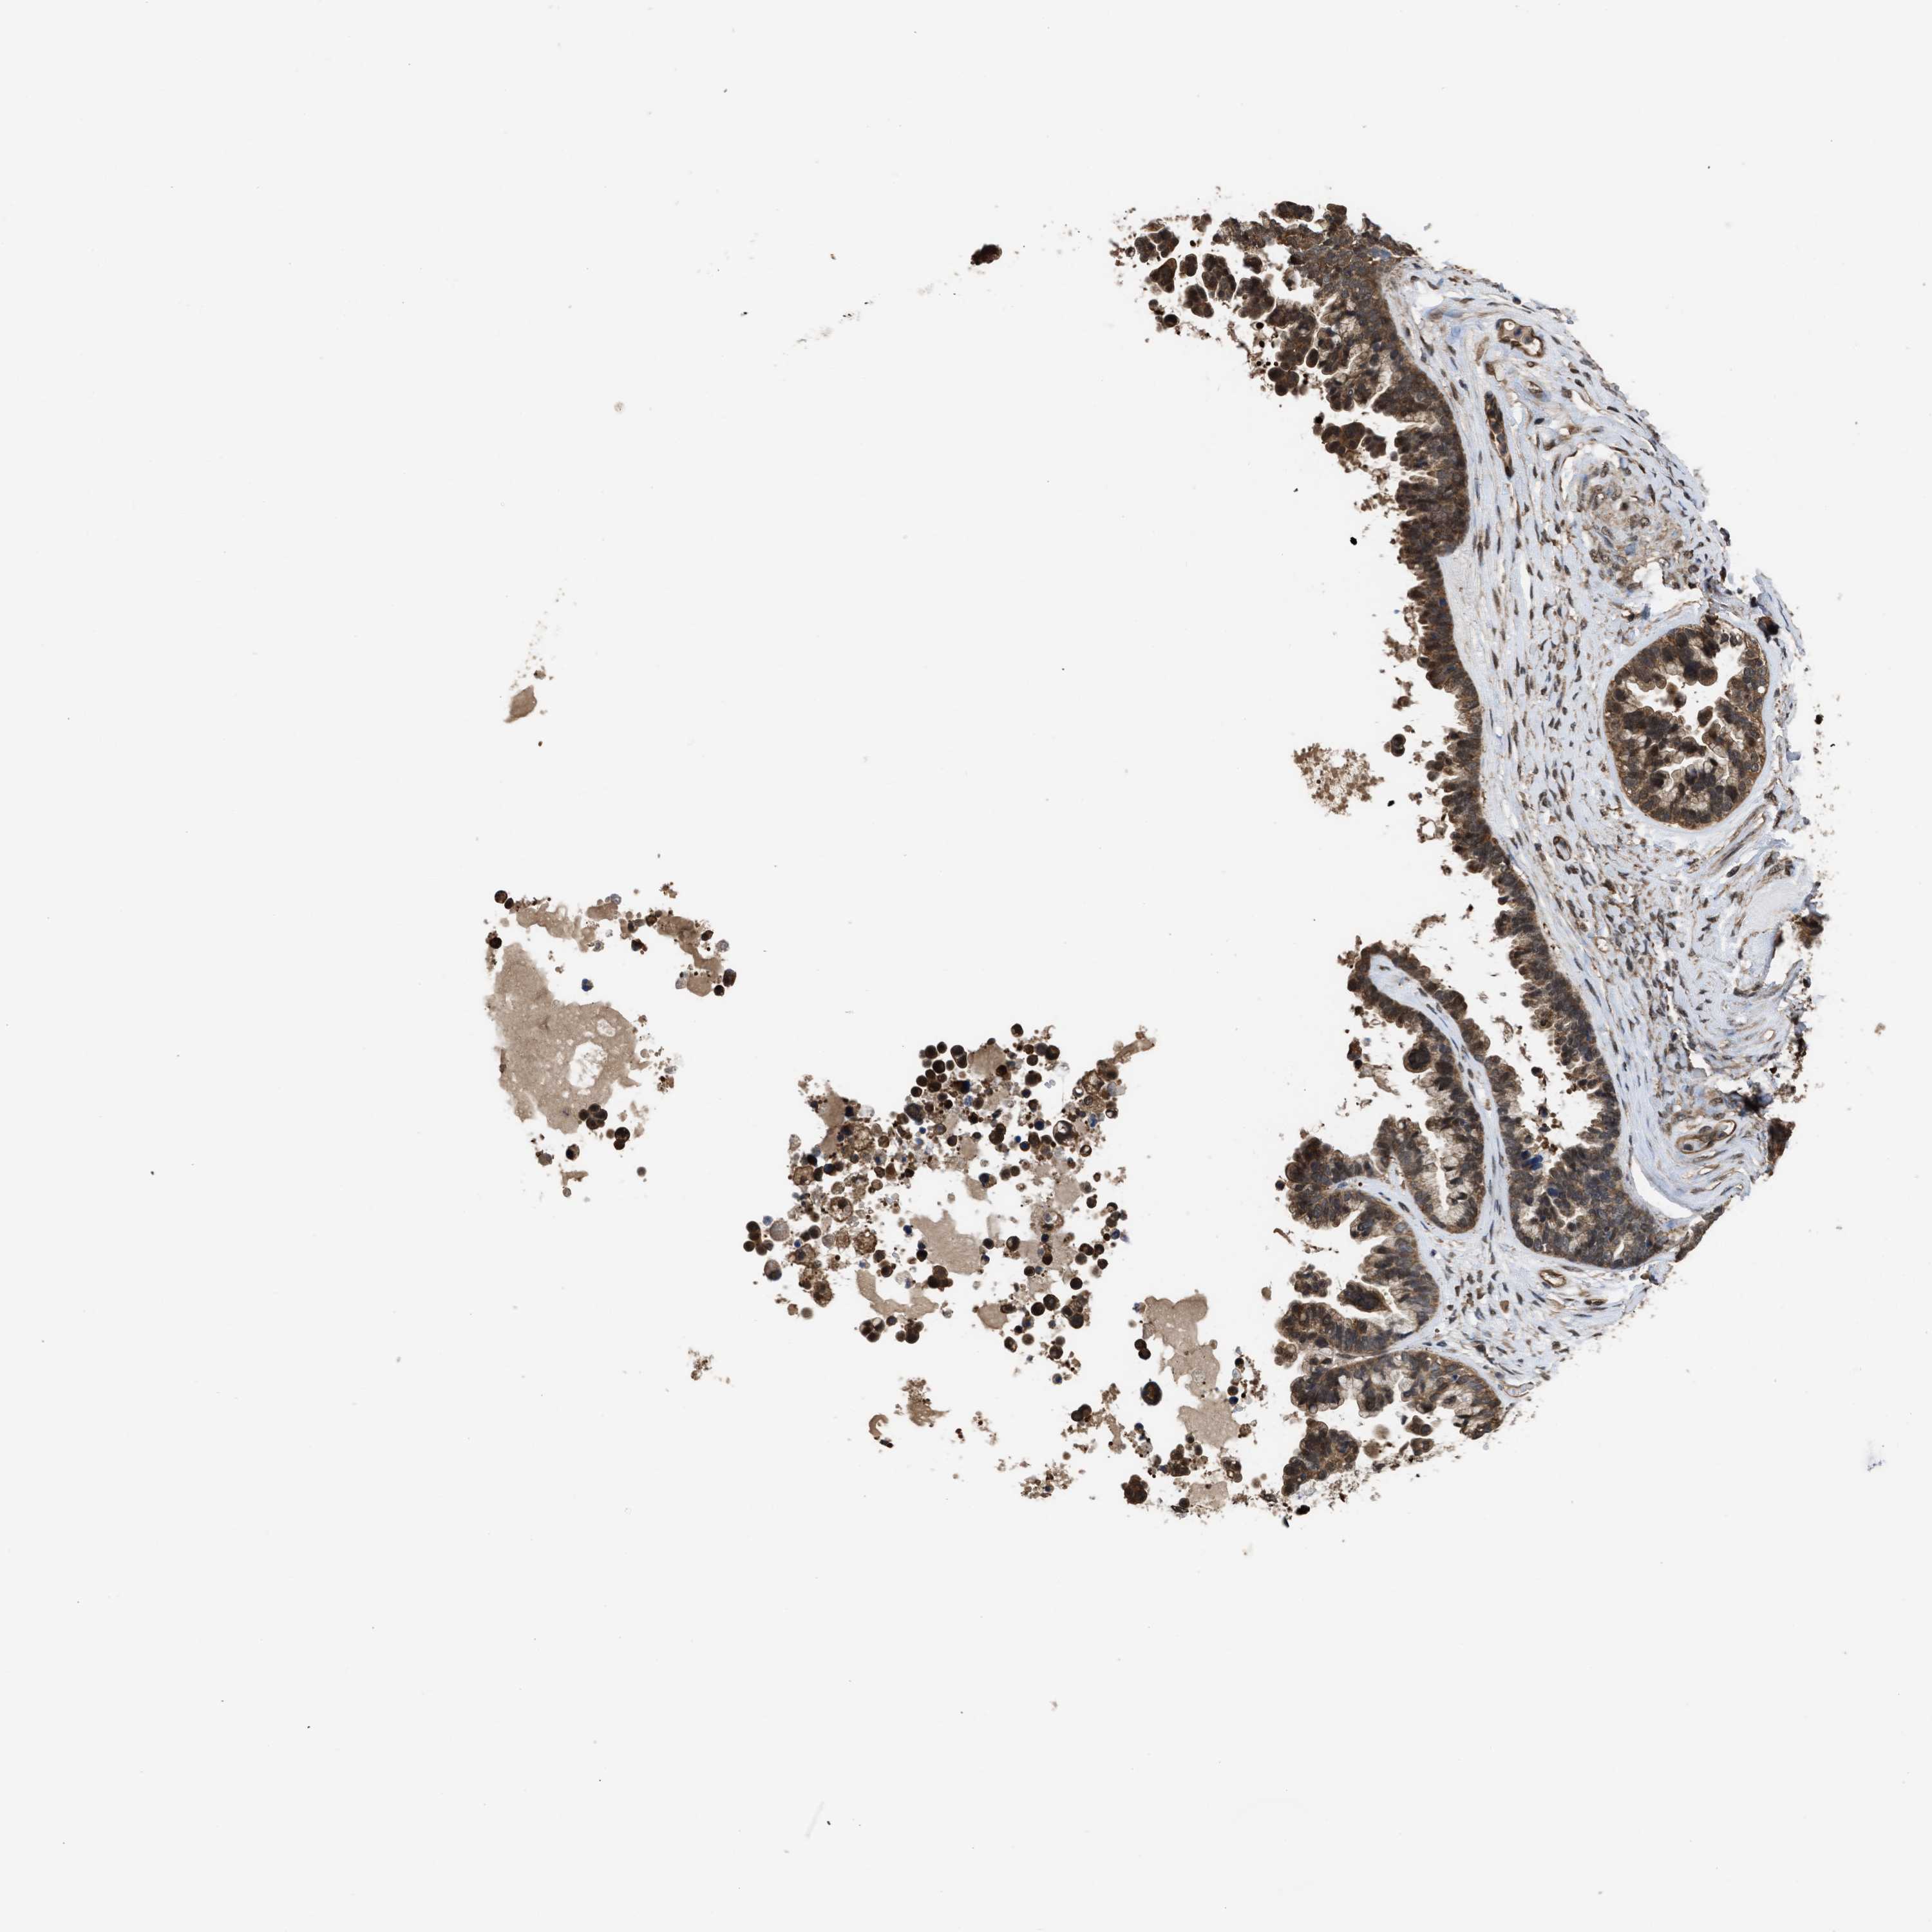

OVARIAN CANCER - Protein expressioni

A mouse-over function shows sample information and annotation data. Click on an image to view it in a full screen mode. Samples can be filtered based on level of antibody staining by selecting one or several of the following categories: high, medium, low and not detected. The assay and annotation is described here.

Note that samples used for immunohistochemistry by the Human Protein Atlas do not correspond to samples in the TCGA dataset.

Antibody stainingi

Antibody staining in the annotated cell types in the current human tissue is reported as not detected, low, medium, or high, based on conventional immunohistochemistry profiling in selected tissues. This score is based on the combination of the staining intensity and fraction of stained cells.

Each image is clickable and will lead to virtual microscopy that enables deeper exploration of all samples and also displays staining intensity scores, fraction scores and subcellular localization as well as patient and tissue information for each sample.

Antibody HPA026918

Antibody CAB013274

Antibody CAB018389

Cystadenocarcinoma, serous, NOS

Carcinoma, endometroid

Cystadenocarcinoma, mucinous, NOS

Carcinoma, NOS